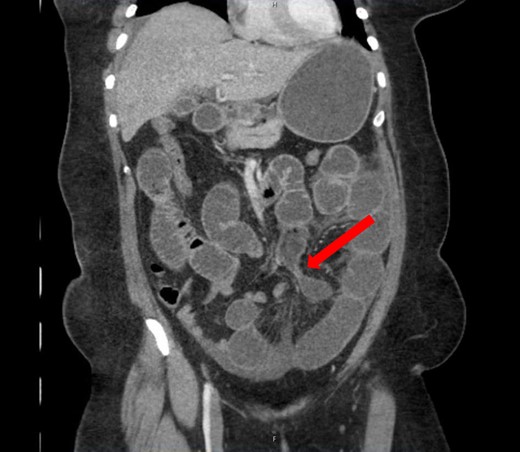

A 40-year-old woman presented to the emergency department with abdominal pain for 4 days. She had previously been seen at an outside hospital 3 days earlier, and was diagnosed with biliary colic. Her pain was constant, and was associated with nausea and vomiting. She had a history of a cesarean section, but no other abdominal surgeries. Her vitals were within normal limits: afebrile at 36.9°C, heart rate 71 beats/minute, blood pressure 143/62 mmHg, respiratory rate 18 breaths/minute, and oxygen saturation 97% on room air. On abdominal exam, she was distended, tender, demonstrated voluntary guarding and was positive for peritonitis. Laboratory values were significant for a white blood cell count of 16.1 K/ul, with 80.2% neutrophils, hemoglobin 14.9 g/dl, hematocrit 45.4%, platelets 349 K/ul and lactic acid 0.9 mEq/L; her chemistry was unremarkable. A computed-tomography (CT) scan of the abdomen and pelvis that was obtained prior to surgical consultation demonstrated the proximal two-thirds of small bowel dilated up to 4 cm, with a sharp transition point in the left mid-abdomen, and collapsed small bowel loops near the cecum. The colon was mostly collapsed. A few distended loops bulged into a paraumbilical hernia, which was 6 cm wide and not the cause of obstruction (Figs 1–3).

Coronal view: arrow pointing to the sharp transition point, where the distal end of the closed loop small bowel herniated through a hole in the sigmoid epiploica, demonstrating collapsed small bowel distally.